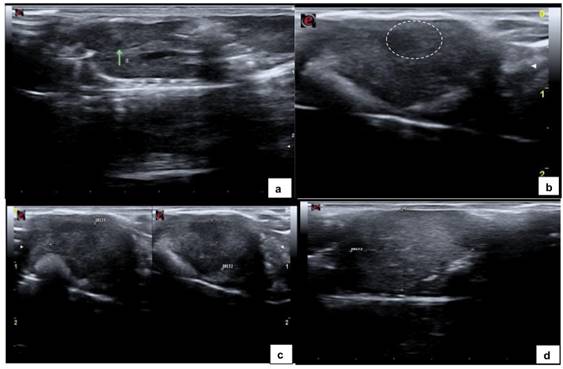

6) Images ranged in appearance from small areas, slightly hypoechoic (Fig. 1a) relative to the surrounding liver parenchyma, with indistinguishable borders identified as scar tissue, to solid, homogeneus hypoechoic mass (Fig. 1b; 1c) and solid, heterogeneous hypoechoic masses with distinct, irregular borders identified as tumors (Fig. 1d);

Ultrasound imaging was obtained from 38 mice, of which 19 (50%) had a homogeneous and normoechoic liver parenchyma and no tumors on gross pathological examination and histologic sections (Fig. 3). In the remaining 19 mice (50%), at least one nodule measuring between 1.2 mm and 17.1 mm in diameter along its longitudinal axis was detected by ultrasound. Liver nodule appeared as:

a) Small hypoechoic structure measuring <3 mm with homogeneous echotexture visualized in the left lobe of the liver in eight histologically negative mice and consistent with scar tissue. These findings, measuring up to 2.8 mm along the longitudinal axis (cranio-caudal diameter), showed no morphological evolution on serial ultrasound imaging and are consistent with scar tissue.

b) Nodule measuring >3 mm visualized in 11 histologically positive mice, of which:

eight appeared as hypoechoic images measuring >3 mm with slightly coarse echotexture and defined borders;

three appeared as predominantly hypoechoic images measuring >10 mm with heterogeneous echotexture and small, sparse pin-point hyperechoic areas (probably representing mineralization), and distinct irregular borders.